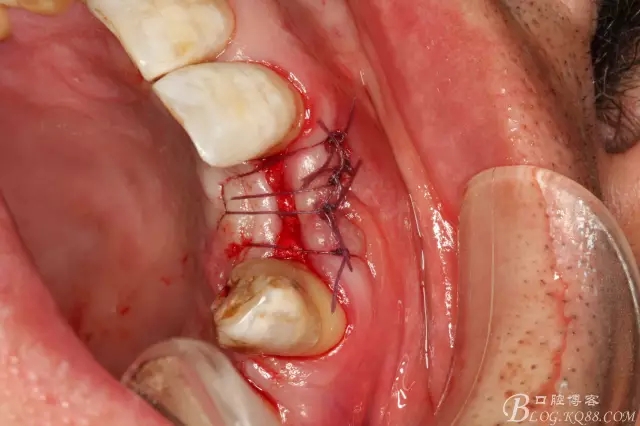

圖6.切開、翻瓣、清理牙槽嵴骨面上的纖維結(jié)締組織。

圖10.縫合